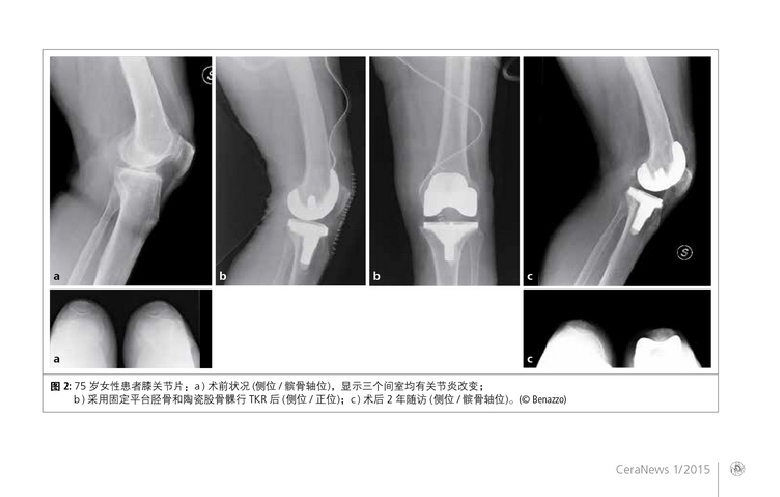

临床病例:疑似或确诊对金属过敏患者的人工膝关节置换